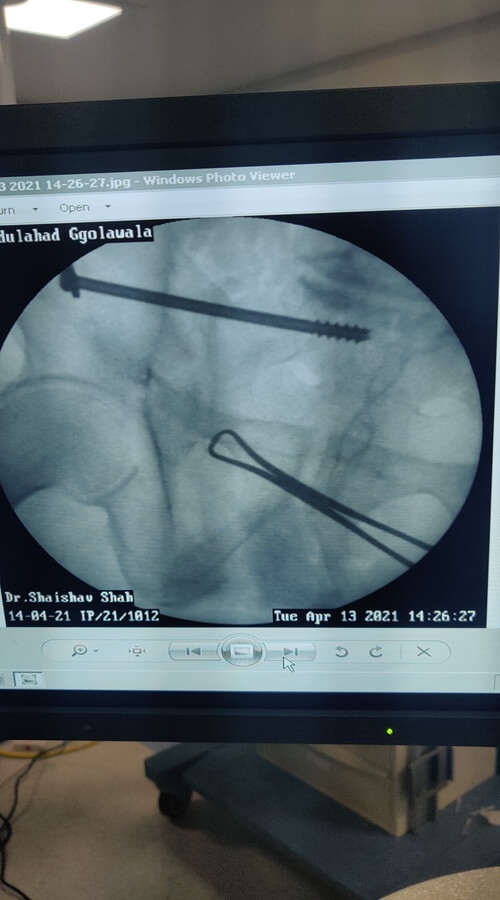

Endoscopic Spine Surgeon

- Successfully Done More Than 5000+ Spine Surgeries

- Successfully Done More Than 1000+ Endoscopic Spine Surgery